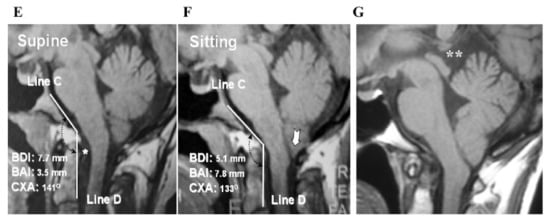

2.4.1. Foramen Magnum Decompression (FMD) for CM-I Type B and CM-Borderline

2.4.3. CCF for CM-I with CCJ Instability

4.2.2. Outcome of CCF for CCJ Instability